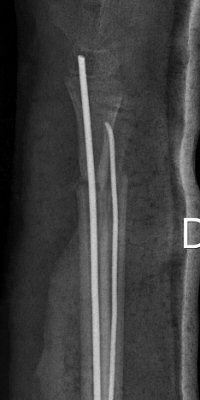

Distala diafysära radius- och ulnafrakturer, opererade med TEN-spikar, sista bilderna läkt efter 7 månader. Alla bilderna är från samma patient.